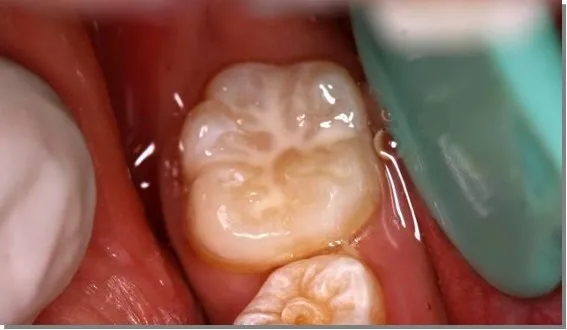

做窝沟封闭前、后